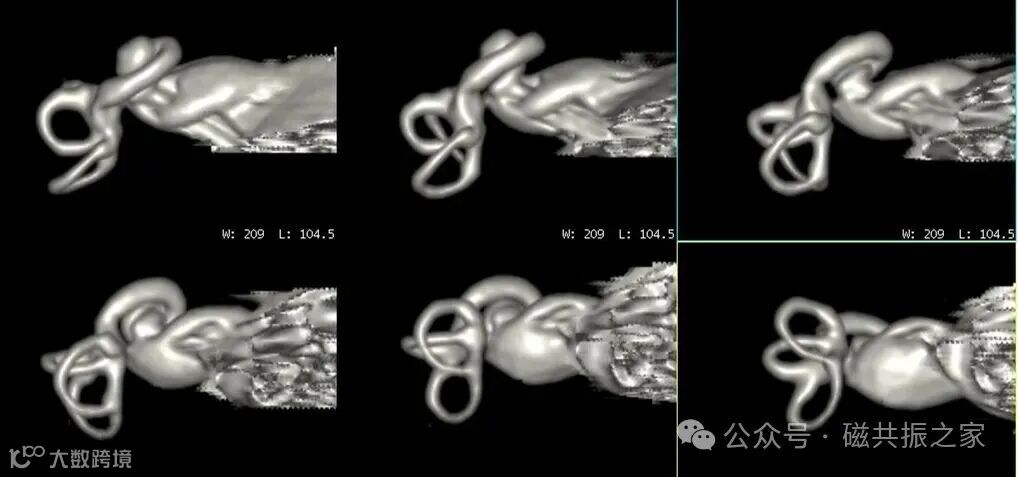

我们知道,IAC成像更强调的是水成像,如上图△为基于3D 重T2WI所获得的耳蜗结构图像。

为了实现多方位的重组与观察,建议采用各项同性的扫描方式,以减少后重建中的失真。

根据方位角度的需求对目标神经进行后重建处理,如上图△,展示的为对单侧面、听神经进行处理。